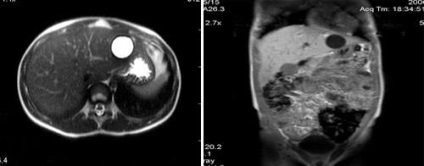

MRI képalkotó hepatocelluláris adenoma a máj

Hepatocelluláris rák (az US - hemangioma).

Hepatocelluláris rák (infiltratív formájában), a másodlagos lymphadenopathia.

Cholangiocelluláris rák (kolangiokarcinóma).